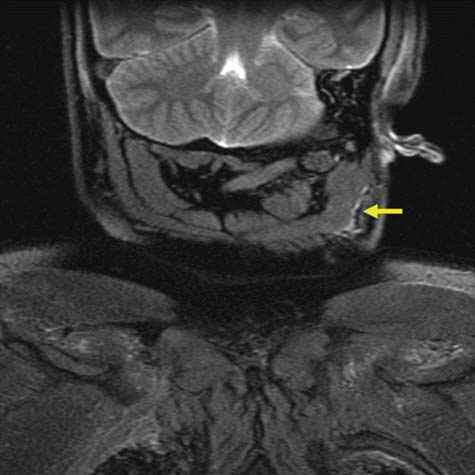

![]() |

In cases of strangling or throttling, a limited amount of pressure is exerted onto the cervical vessels, thus giving rise to petechial hemorrhages. However, they are rarely encountered in cases of classic suicidal hanging. In these cases, the afferent and efferent blood vessels to the head are typically-if the noose is behind the mandibular angle-equally compressed. Therefore, no petechial hemorrhages are to be expected. Here, a thorough medicolegal inspection can reveal telltale imprints to the neck, even if the noose has been removed. Slight and superficial abrasions of the skin can often lead to the correct diagnosis. Additional hemorrhages of the subcutaneous tissue and the cervical musculature can, according to our experience, further support this hypothesis (Figure D3.2.18), although recent literature is uncertain as to the overall significance [17,18]. Furthermore, fractures of the hyoid bone or thyroid horns, a finding easily detected in postmortem MSCT (Figure D3.2.19 and Figure D3.2.20), give rise to the diagnosis blunt trauma to the neck [19,20].

These situations, when faced by inexperienced or all too experienced colleagues, can give rise to the premature diagnosis suicide by hanging. Unfortunately, it cannot be stressed enough that scene findings, no matter how convenient they may be, should always be seen in a critical light in the context as a whole. If only a single finding does not fit into the whole scene, then the examination should be performed with even more ardor and scrutiny than usual. The question of a homicide by prior choking and subsequent hanging to imitate a suicidal hanging must always be addressed [21]. Apart from the crime scene investigation, the medicolegal examination is of utmost importance. Here, several techniques, such as the assessment of muscle histology [22], can be of assistance. As Aghayev et al. [23] show, the examination of the posterior cricoarytenoid muscle can serve as an imminently important finding in cases of suspected blunt trauma to the neck such as in choking.

Postmortem imaging, especially in the form of MRI, can visualize such lesions that would otherwise only be detected at autopsy. The pathology and forensic imaging of choking is dealt with in further detail in Chapter D3.7, "Strangulation." Obviously, osseous lesions are easily seen in postmortem MSCT. Hyoid and thyroid fractures can give clues as to whether a blunt trauma occurred to the neck. A caveat is nevertheless to be made: Anatomical variations of the thyroid and hyoid structures may give the impression of such violent injuries. In these cases, a surrounding hemorrhage-as found in traditional autopsies-must be looked for. The lack of such hemorrhages in postmortem imaging deems a vital or fresh fracture of the throat skeleton rather unlikely.